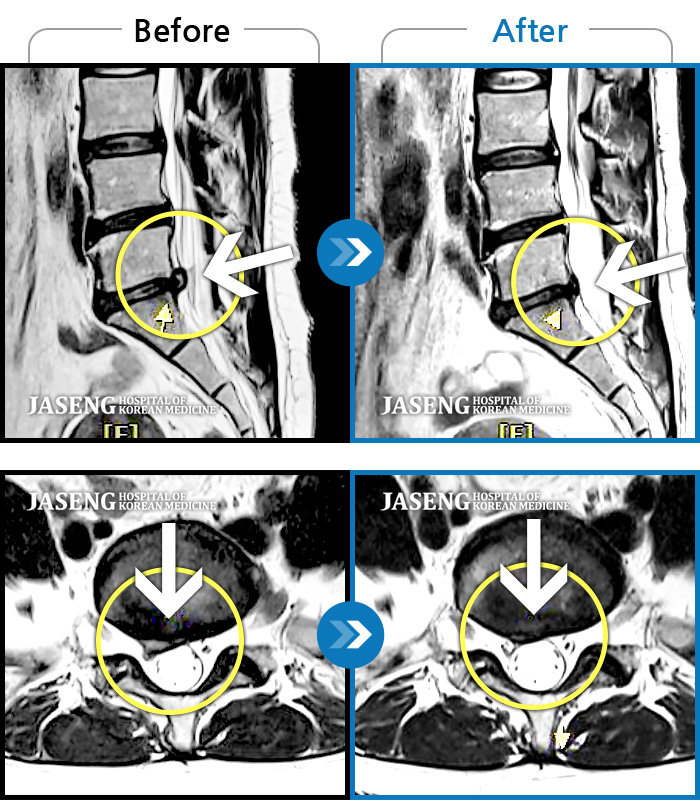

허리디스크

도움받은 사례

광주 · 장영우 원장

양측 허리부터 좌측 다리까지 이어지는 저림과 통증으로 걷기 힘들어 내원하였습니다.

촬영시기

2024.11.22 ~ 2025.05.16

2025.05.30

조회수 285